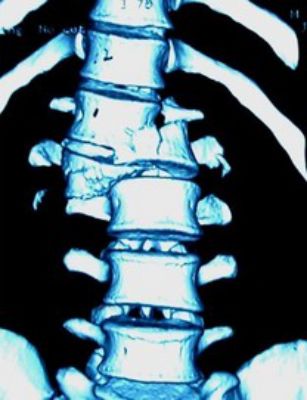

2、CT:可显示椎体的骨折情况,可显示有无碎骨片突出于椎管内,计算椎管前后径损失了多少,不能显示脊髓受损情况。(平扫、薄扫、三维、表面重建等)

(2)爆裂骨折

椎体压缩骨折的一种特殊形式,椎体呈粉碎骨折,骨折块向四周移位,向后移位可压迫脊髓、神经,椎体前后径和横径均增加,两侧椎弓根距离加宽,椎体高度减小。